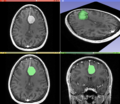

Information can take the form of images, sound, video or other multimedia. Bits of information can be streamed via signals. Its processing is the central notion of informatics, the European view on computing, which studies information processing algorithms independently of the type of information carrier – whether it is electrical, mechanical or biological. This field plays important role in information theory, telecommunications, information engineering and has applications in medical image computing and speech synthesis, among others. What is the lower bound on the complexity of fast Fourier transform algorithms? is one of the unsolved problems in theoretical computer science.

| FFT algorithms | Image processing | Speech recognition | Data compression | Medical image computing | Speech synthesis |